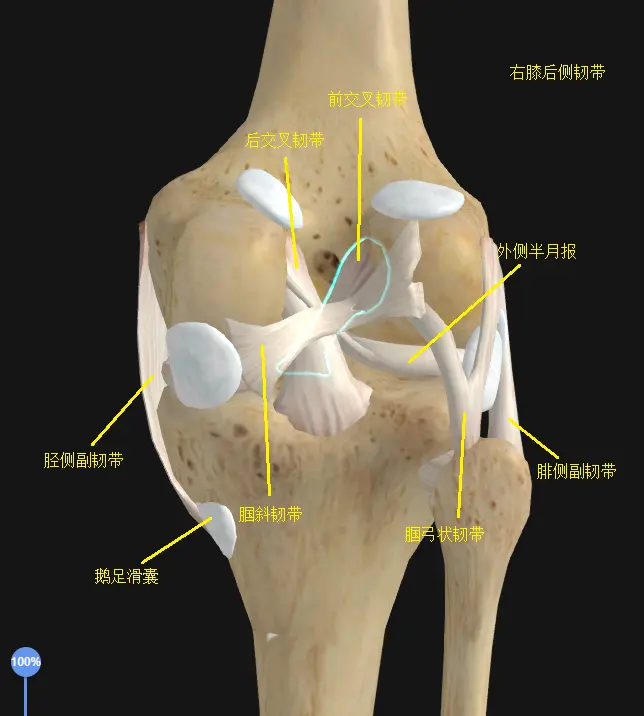

膝关节在功能解剖上有前侧伸膝功能的股四头肌和屈膝功能的缝匠肌,有后侧屈膝功能的半腱肌半膜肌,股二头肌,腘肌,腓肠肌。倒不是说没有在左右两侧跨越膝关节的肌肉(比如引起髂胫束综合征的阔筋膜张肌-髂胫束就是在外侧跨过了膝关节),而是膝关节周围有一圈不具备收缩性的韧带加固,使膝关节失去左右活动的能力,相应的获得了超强稳定性。

膝关节在功能解剖上有前侧伸膝功能的股四头肌和屈膝功能的缝匠肌,有后侧屈膝功能的半腱肌半膜肌,股二头肌,腘肌,腓肠肌。倒不是说没有在左右两侧跨越膝关节的肌肉(比如引起髂胫束综合征的阔筋膜张肌-髂胫束就是在外侧跨过了膝关节),而是膝关节周围有一圈不具备收缩性的韧带加固,使膝关节失去左右活动的能力,相应的获得了超强稳定性。

上述所有肌肉韧带的特点都是不具备膝关节左右活动,即外展内收功能的,膝关节周围的肌肉只有屈伸功能,以及“在屈膝位上,很少量的旋转功能”。它所有的构造(骨,软骨,韧带,肌肉,软组织等…)从上到下从内到外都是为了屈伸功能和承重服务的,这些解剖结构决定了在实际使用场景中,膝关节运动要避免旋转和左右两侧活动的力。

了解了膝关节的结构之后我们可以知道,膝关节的稳定性是由关节周围的肌肉韧带来完成的,在前后的屈伸过程中伸膝肌和屈膝肌可以控制动态稳定,而膝关节不存在外展内收功能,所以无法对膝关节左右方向上的稳定进行动态控制。如果出现了类似左右方向上的力,维持膝关节左右方向的静态稳定的任务会落到周围韧带上,于是韧带压力过大,这是我们不希望出现的事。

除了髋和踝对下肢的控制,其实也有越过膝关节的肌肉能够控制大腿和小腿的旋转,比如伸髋屈膝功能的半腱肌半膜肌和股二头肌,它们一左一右附着到小腿上,在屈膝位上就有了使小腿旋转的能力,屈膝时半腱肌半膜肌能够使小腿内旋,股二头肌可以使小腿外旋,如果站立时有一方极度的紧张缩短或松弛无力,两者相对失衡也会影响膝关节的对位。

还有一块小的肌肉是腘肌,不同于腘绳肌的是它很小,像半块补丁一样在膝关节后侧,可以屈膝也可以在屈膝位上使小腿内旋。

缝匠肌也是有屈膝时使小腿内旋的功能。